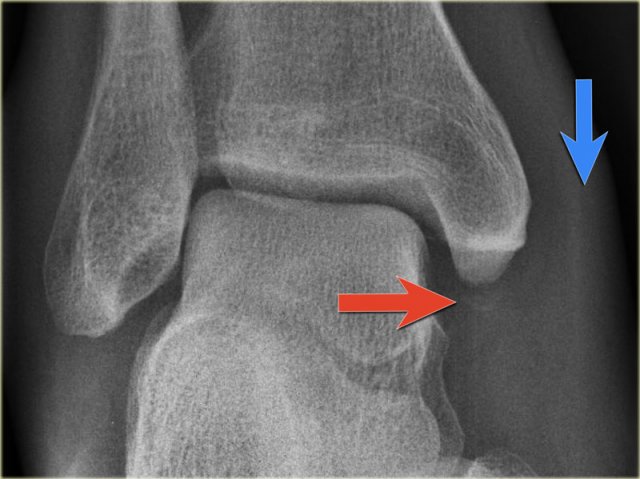

Example 4

• Basic interpretation

Fracture of the lateral malleolus starting anteriorly at the level of the joint extending proximally posteriorly.

• Classification

The fracture is classified according to Weber as a type B fracture.

According to Lauge Hansen the oblique fibular fracture indicates that this is a Supination Exorotation injury stage 2 or higher.

• Re-examination

Look for stage 3 and stage 4.

There are subtle findings which indicate a fracture of the posterior malleolus. Normally you probably would not have noticed these.

On the lateral view the posterior cortex of the tibia is interrupted indicating a fracture (blue arrow).

Even on the AP-view there are subtle findings that indicate a fracture (red arrows).

There is a widened medial clear space, which indicates a rupture of the medial collateral band, i.e. stage 4.

• Final report

Weber B fracture. According to Lauge-Hansen this is a SER stage 4.

This is an unstable fracture with dislocation that needs surgical repair.